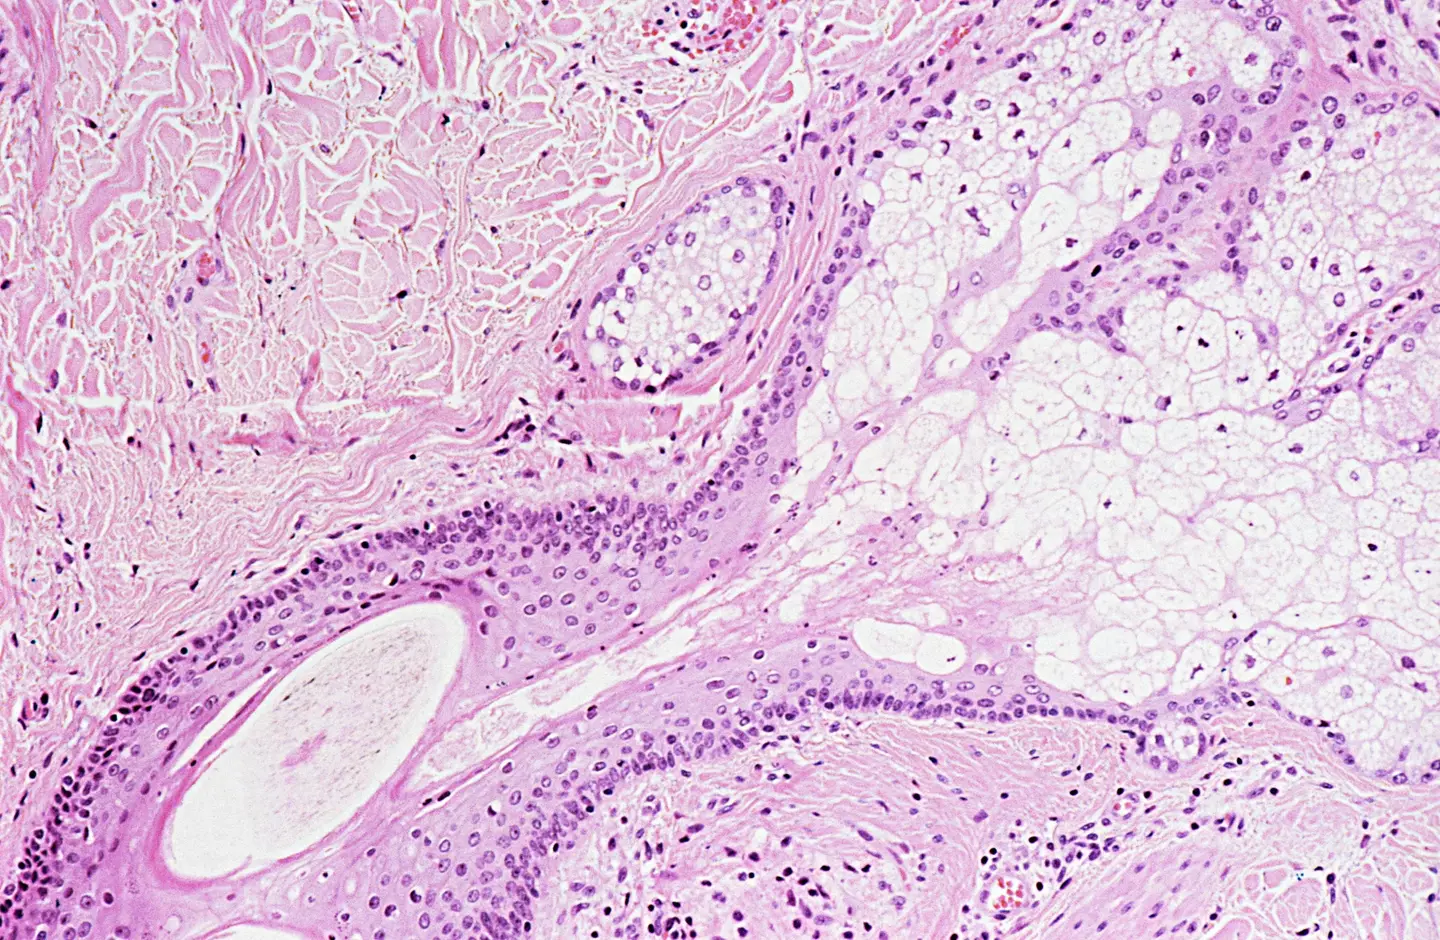

Scientists have developed an ‘exciting’ new method to reverse ageing in human skin cells by up to 30 years, which they say is the longest ‘re-programming’ technique ever achieved.

In a new study, published in eLife, the team of researchers revealed how they were able to partly restore the function of older cells, while also renewing the biological age.

In trials that simulated a skin wound, the team found that the partially rejuvenated cells showed signs of behaving more like youthful cells.

The experts at the Babraham Institute developed the first ‘maturation phase transient reprogramming’ (MTPR), where ‘reprogramming factors are expressed until this rejuvenation point followed by withdrawal of their induction’.

The authors wrote: “The magnitude of rejuvenation instigated by MTPR appears substantially greater than that achieved in previous transient reprogramming protocols.

“In addition, MPTR fibroblasts produced youthful levels of collagen proteins, and showed partial functional rejuvenation of their migration speed.”

While the research is still in its early stages, scientists believe the findings could help revolutionalise regenerative medicine, particularly if the approach can be replicated in other cell types.

The team explained how ageing is the gradual decline in ‘organismal fitness’, which occurs over time and leads to tissue dysfunction and disease.

At the cellular level, ageing is associated with ‘reduced function, altered gene expression and a perturbed epigenome’.

Regenerative biology aims to repair or replace cells, including old ones, with one of the most important tools being to create ‘induced stem cells’. However, this wipes the cells of their function, in turn giving them the potential to become any type of cell.

The new method, which is based on Nobel Prize-winning technique used to make stem cells, solves the problem by simply erasing cell identity through reprogramming part of the way through the process.